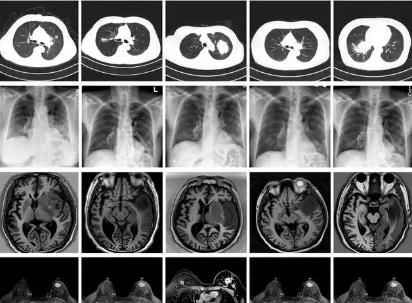

我國科學(xué)家建立生成式模型為醫(yī)學(xué)AI訓(xùn)練提供技術(shù)支持

北京大學(xué)與溫州醫(yī)科大學(xué)的研究團(tuán)隊(duì)建立一種生成式多模態(tài)跨器官醫(yī)學(xué)影像基礎(chǔ)模型(MINIM),可基于文本指令以及多器官的多種成像方式,合成海量的高質(zhì)量醫(yī)學(xué)影像數(shù)據(jù),為醫(yī)學(xué)影像大模型的訓(xùn)練、精準(zhǔn)醫(yī)療及個(gè)性化診療等提供有力...